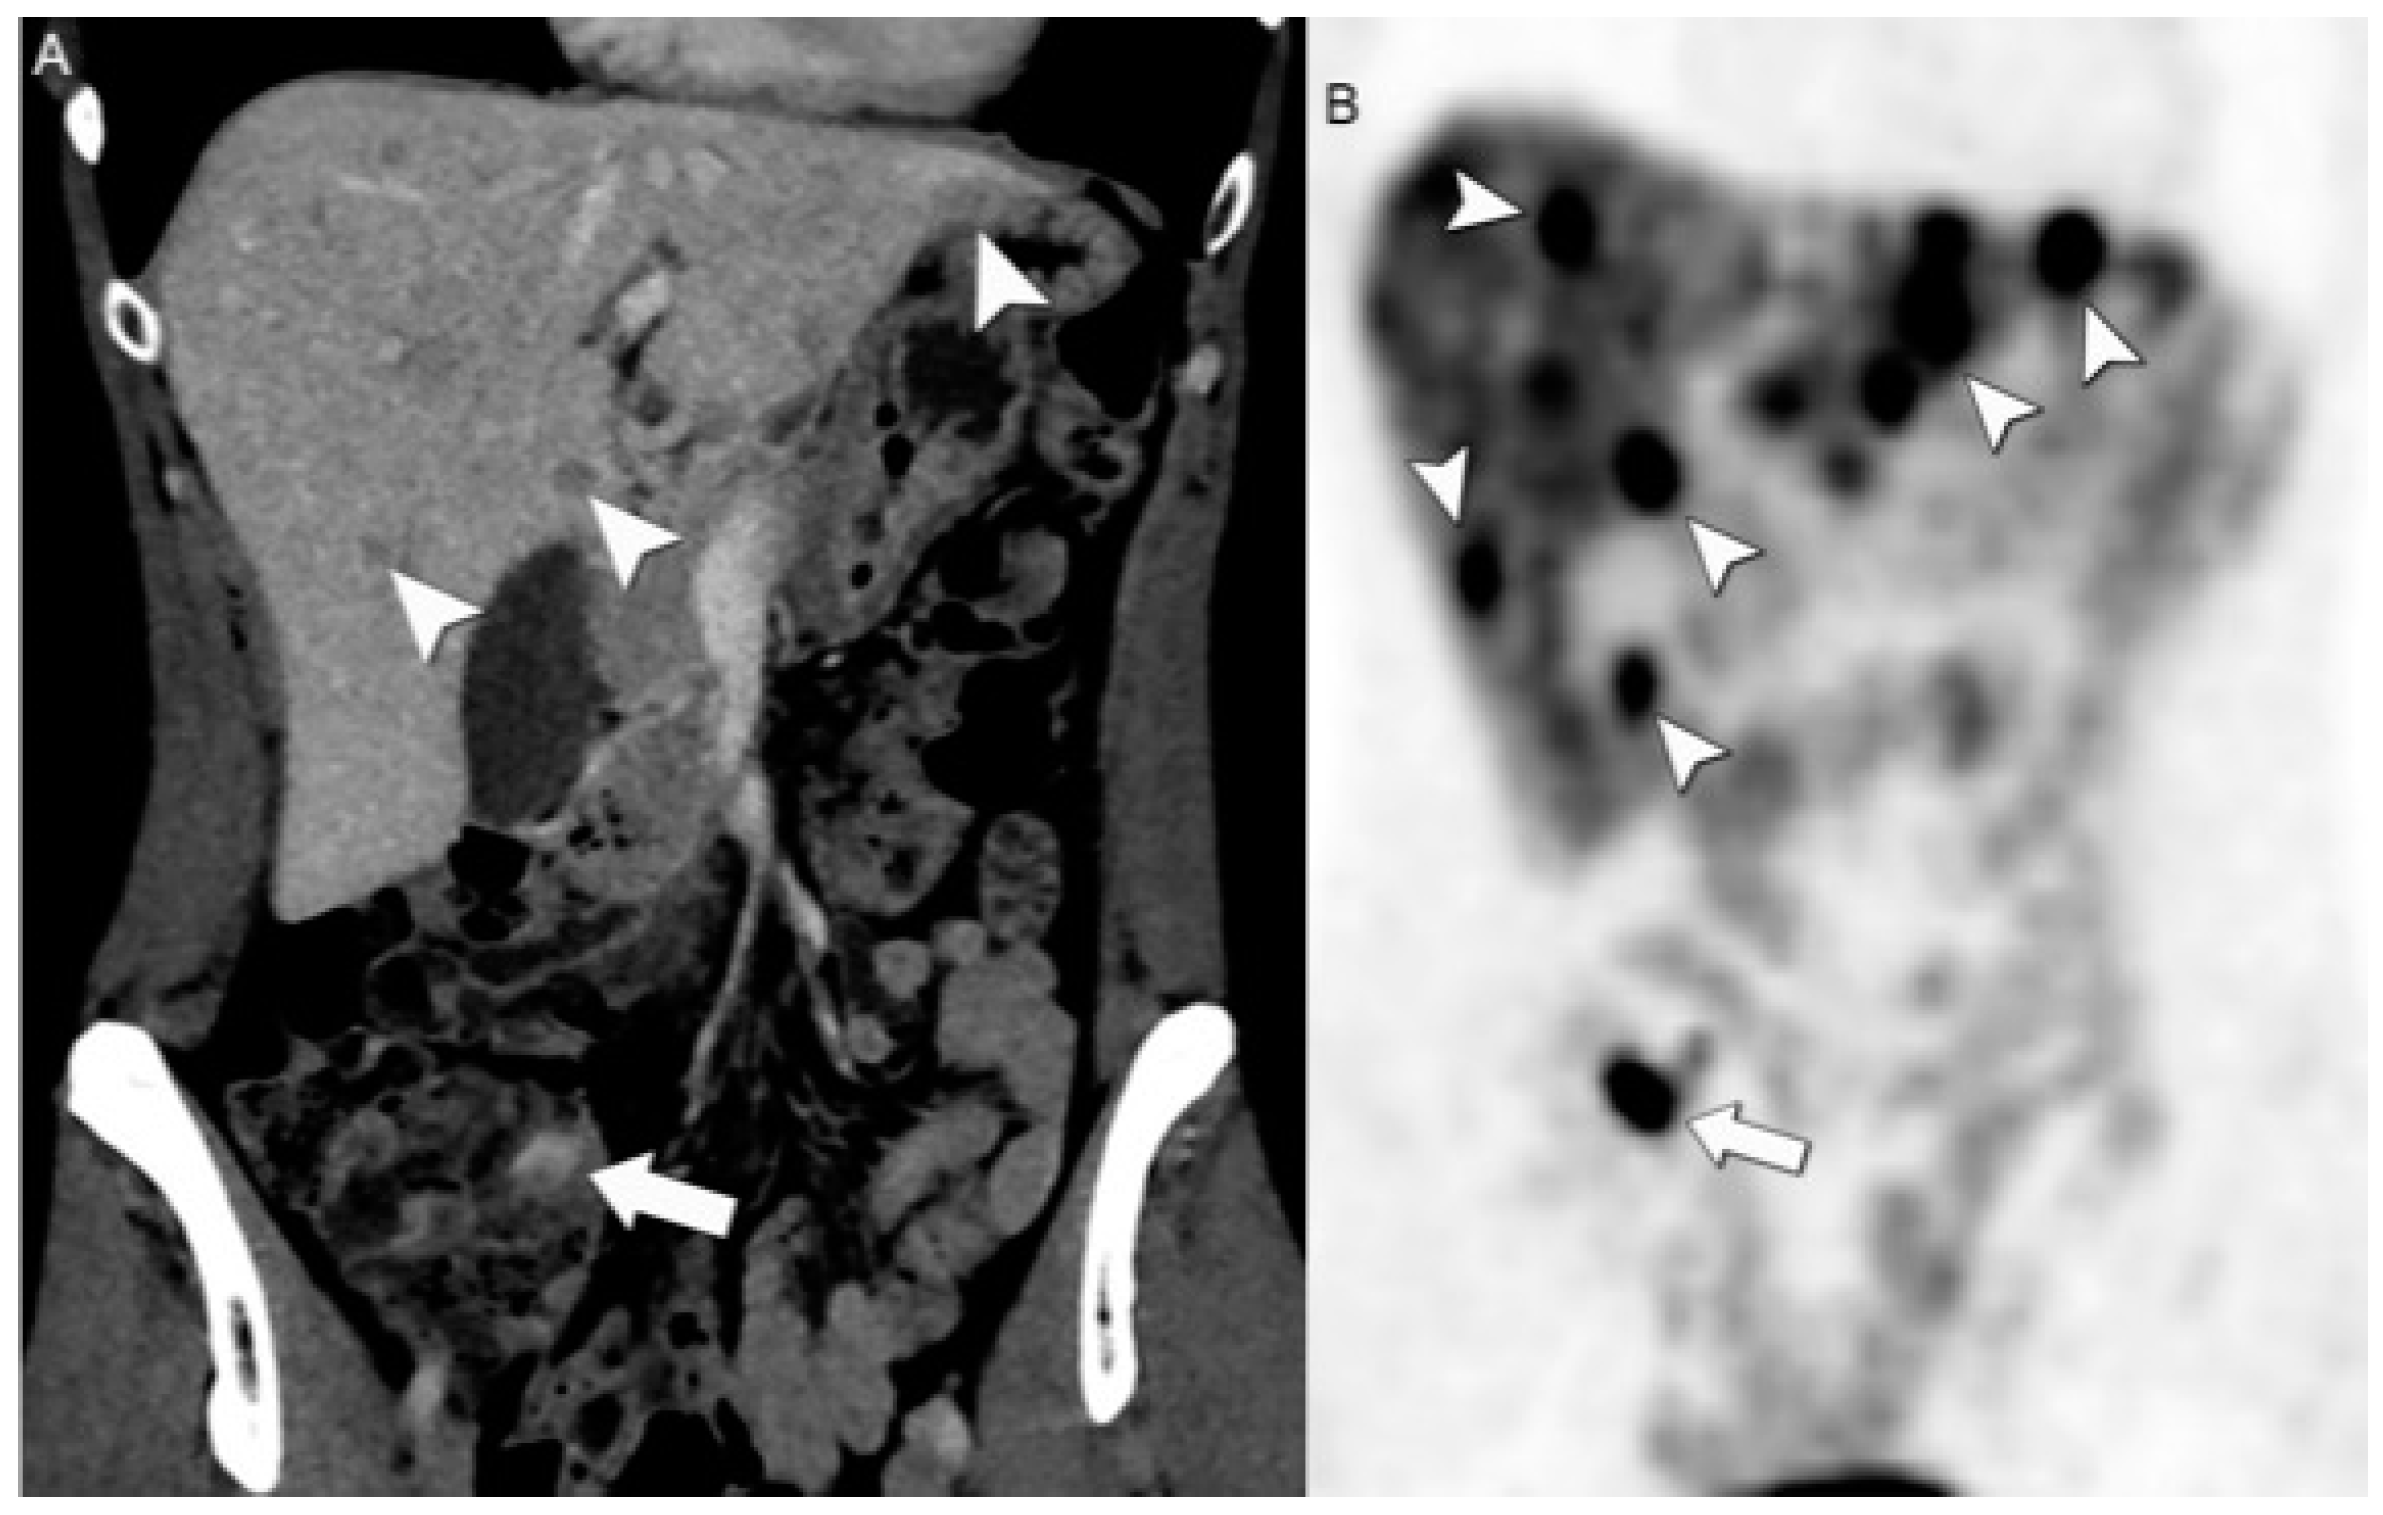

- Karfis, I.; Marin, G.; Levillain, H.; Drisis, S.; Muteganya, R.; Critchi, G.; Taraji-Schiltz, L.; Guix, C.A.; Shaza, L.; Elbachiri, M.; et al. Prognostic Value of a Three-Scale Grading System Based on Combining Molecular Imaging with 68Ga-DOTATATE and 18F-FDG PET/CT in Patients with Metastatic Gastroenteropancreatic Neuroendocrine Neoplasias. Oncotarget 2020, 11, 589–599. [Google Scholar] [CrossRef] [PubMed]

- Graf, J.; Pape, U.-F.; Jann, H.; Denecke, T.; Arsenic, R.; Brenner, W.; Pavel, M.; Prasad, V. Prognostic Significance of Somatostatin Receptor Heterogeneity in Progressive Neuroendocrine Tumor Treated with Lu-177 DOTATOC or Lu-177 DOTATATE. Eur. J. Nucl. Med. Mol. Imaging 2020, 47, 881–894. [Google Scholar] [CrossRef]

- Binderup, T.; Knigge, U.; Johnbeck, C.B.; Loft, A.; Berthelsen, A.K.; Oturai, P.; Mortensen, J.; Federspiel, B.; Langer, S.W.; Kjaer, A. 18F-FDG PET Is Superior to WHO Grading as a Prognostic Tool in Neuroendocrine Neoplasms and Useful in Guiding PRRT: A Prospective 10-Year Follow-up Study. J. Nucl. Med. 2021, 62, 808–815. [Google Scholar] [CrossRef] [PubMed]

- Chan, D.L.; Pavlakis, N.; Schembri, G.P.; Bernard, E.J.; Hsiao, E.; Hayes, A.; Barnes, T.; Diakos, C.; Khasraw, M.; Samra, J.; et al. Dual Somatostatin Receptor/FDG PET/CT Imaging in Metastatic Neuroendocrine Tumours: Proposal for a Novel Grading Scheme with Prognostic Significance. Theranostics 2017, 7, 1149–1158. [Google Scholar] [CrossRef]

- Hindié, E. The NETPET Score: Combining FDG and Somatostatin Receptor Imaging for Optimal Management of Patients with Metastatic Well-Differentiated Neuroendocrine Tumors. Theranostics 2017, 7, 1159–1163. [Google Scholar] [CrossRef]